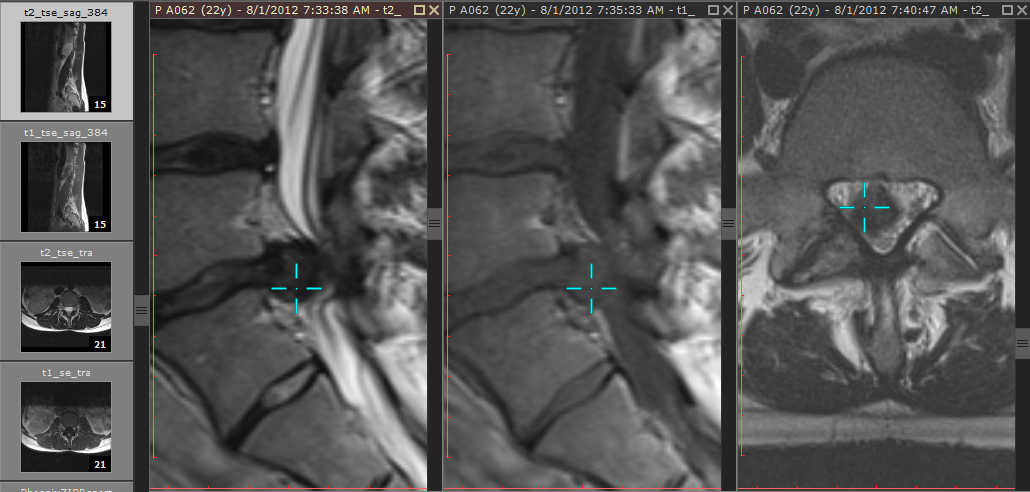

浏览不同图像平面的序列时(例如磁共振检查),3D 光标工具可帮助更好地关联解剖结构。它显示为蓝色十字准线光标,在所有图像上标记同一个三维空间中的对应点。

按住 Ctrl + Shift 并点击鼠标左键,可显示 3D 光标。按住左键拖动鼠标,可在活动视口中移动光标位置,其他视口中的图像将自动滚动到最接近该 3D 光标的切面。松开鼠标后光标消失。3D 光标激活时,参考线会暂时隐藏。启用电影播放模式时无法激活 3D 光标。

如果光标位置与图像平面有一定距离(且无法找到更接近的图像平面),光标将显示为红色。